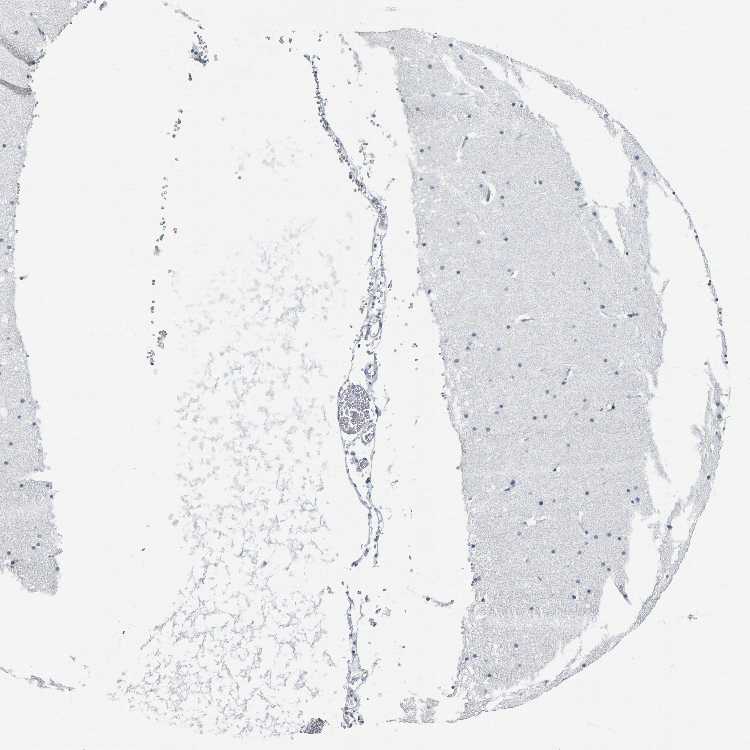

CEREBELLUM - Antibody stainingi

Antibody staining in the annotated cell types in the current human tissue is reported as not detected, low, medium, or high, based on conventional immunohistochemistry profiling in selected tissues. This score is based on the combination of the staining intensity and fraction of stained cells.

Each image is clickable and will lead to virtual microscopy that enables deeper exploration of all samples and also displays staining intensity scores, fraction scores and subcellular localization as well as patient and tissue information for each sample.

Antibody HPA010973Antibody CAB016734

Purkinje cells Not detectedNot detected

Cells in granular layer Not detectedNot detected

Cells in molecular layer Not detectedNot detected